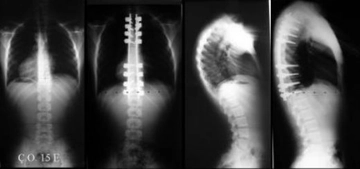

Kifoz, omurganın üst kısmında meydana gelen bir eğrilik olup, bireylerde duruş bozukluklarına ve çeşitli sağlık sorunlarına yol açabilir. Bu durum, özellikle gençler ve yaşlılar arasında yaygın olarak görülebilmektedir. Kifoz egzersizleri, bu durumu düzeltmeye yardımcı olabilen önemli bir tedavi yöntemidir. Bu makalede, kifozun tanımı, sebepleri, belirtileri, egzersizlerin önemi ve uygulanışı üzerinde durulacaktır. Kifoz Nedir?Kifoz, omurganın normal eğriliğinin aşırı artışı ile karakterize edilen bir durumdur. Omurganın üst kısmında meydana gelen bu eğrilik, genellikle "kambur" olarak adlandırılır. Kifoz, doğuştan olabileceği gibi, yaşlanma, travma, osteoporoz gibi durumlar sonucunda da gelişebilir. Kifozun SebepleriKifozun birçok nedeni bulunmaktadır. Bunlar arasında:

SonuçKifoz, bireylerin yaşam kalitesini olumsuz yönde etkileyebilen bir durumdur. Ancak, uygun egzersizler ve düzenli uygulamalar ile bu durum kontrol altına alınabilir. Kifoz egzersizleri, omurganın sağlığını korumak ve duruş bozukluklarını düzeltmek için önemli bir araçtır. Sağlıklı bir yaşam için, bireylerin egzersiz alışkanlıklarını benimsemeleri ve bu konuda uzmanlardan destek almaları önerilmektedir. Ekstra Bilgiler: Kifoz tedavisinde egzersizlerin yanı sıra, fizik tedavi, masaj, ortopedik cihazlar ve cerrahi müdahale gibi diğer tedavi yöntemleri de bulunmaktadır. Kifozun şiddeti ve bireyin genel sağlık durumu, tedavi yöntemlerinin belirlenmesinde önemli bir rol oynamaktadır. |